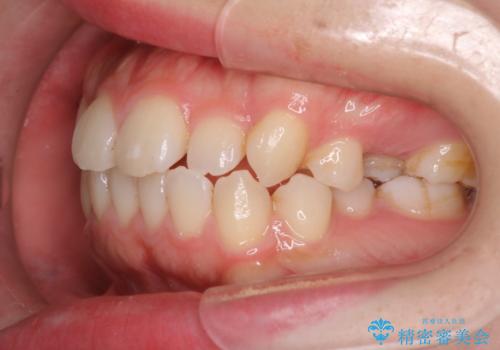

- 患者様は歯並びの乱れを気にされて来院されました。特に小臼歯の捻転(ねじれ)が強く、見た目だけでなく噛み合わせにも影響がありました。できるだけ目立たない方法を希望されていたため、インビザライン(マウスピース矯正)を基本としつつ、より精密な動きが必要な部分にはワイヤー矯正を併用する計画を立てました。また、小臼歯の捻転については**部分矯正(MTM:Minor Tooth Movement)**を取り入れ、効率的に改善を目指しました。

まず、全体の歯並びを整えるためにインビザラインを使用し、徐々に理想的な位置へと歯を移動させました。一方で、ねじれの強い小臼歯に対しては、**部分的なワイヤー矯正(MTM)**を行い、より精密なコントロールを実施。約2年の治療期間を経て、歯並びと噛み合わせが整い、見た目の美しさだけでなく、機能的な改善も達成しました。患者様からは「自然な仕上がりで、自信を持って笑えるようになった」と喜びの声をいただきました。